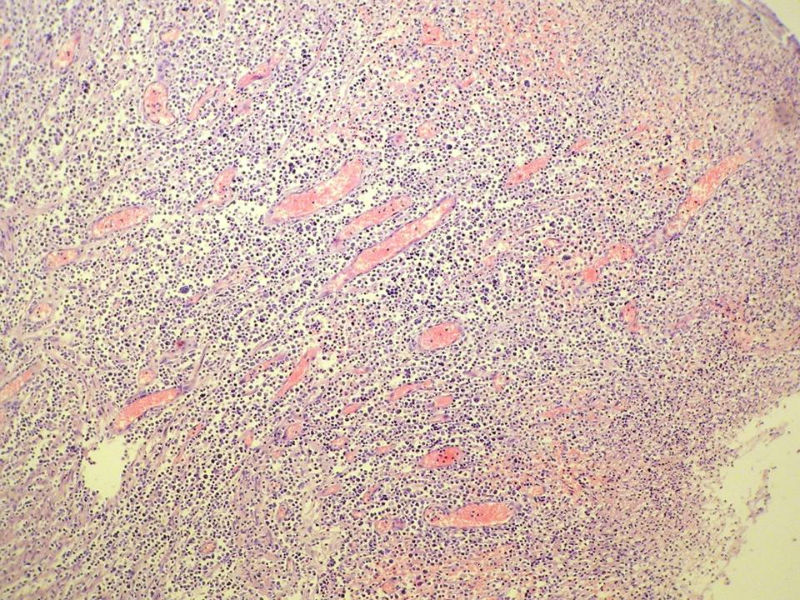

女,53岁,横结肠有9X6厘米大小溃疡,手术切除。

中老年人,溃疡很大,可见淋巴浆细胞样细胞弥漫浸润,散在大细胞,疑非霍奇颈淋巴瘤,倾向MALT伴浆样分化,不知是否破坏肌层?可否传肌层图?需IHC标记,鉴别淋巴瘤、腺癌及其它。

肉眼观仅是溃疡?有没有肠壁增厚、隆起?周围粘膜情况?肌层情况?有淋巴浆细胞样细胞、中心细胞,散在少量不成片的大细胞,不排除MALToma伴大细胞转化。

本例肉眼溃疡如溃疡性结肠炎,肠壁无明显增厚,表面辅以坏死,溃疡边缘稍隆起。镜下淋巴样细胞局限在粘膜层,肌层未见。谢谢!